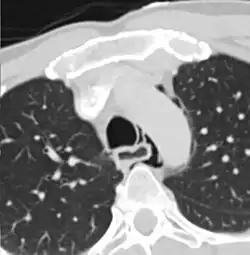

Axial CT image through the upper chest showing extraluminal air (Pneumomediastinum) surrounding the trachea and esophagus

The diagnosis of Boerhaave syndrome is suggested on the plain chest radiography and confirmed by chest CT scan. The initial plain chest radiograph is almost always abnormal in patients with Boerhaave syndrome and usually reveals mediastinal or free peritoneal air as the initial radiologic manifestation. With cervical esophageal perforations, plain films of the neck show air in the soft tissues of the prevertebral space.

Hours to days later, pleural effusion(s) with or without pneumothorax, widened mediastinum, and subcutaneous emphysema is typically seen. CT scan may show esophageal wall edema and thickening, extraesophageal air, periesophageal fluid with or without gas bubbles, mediastinal widening, and air and fluid in the pleural spaces, retroperitoneum or lesser sac.